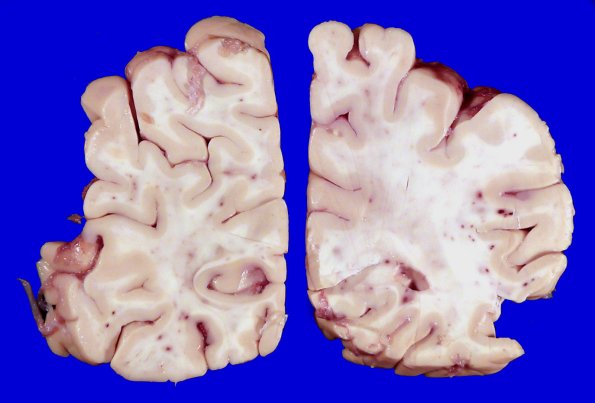

12A3 Fat Embolism (Case 12) Gross _2

In this section a few gray or gray/white junction hemorrhages were seen.